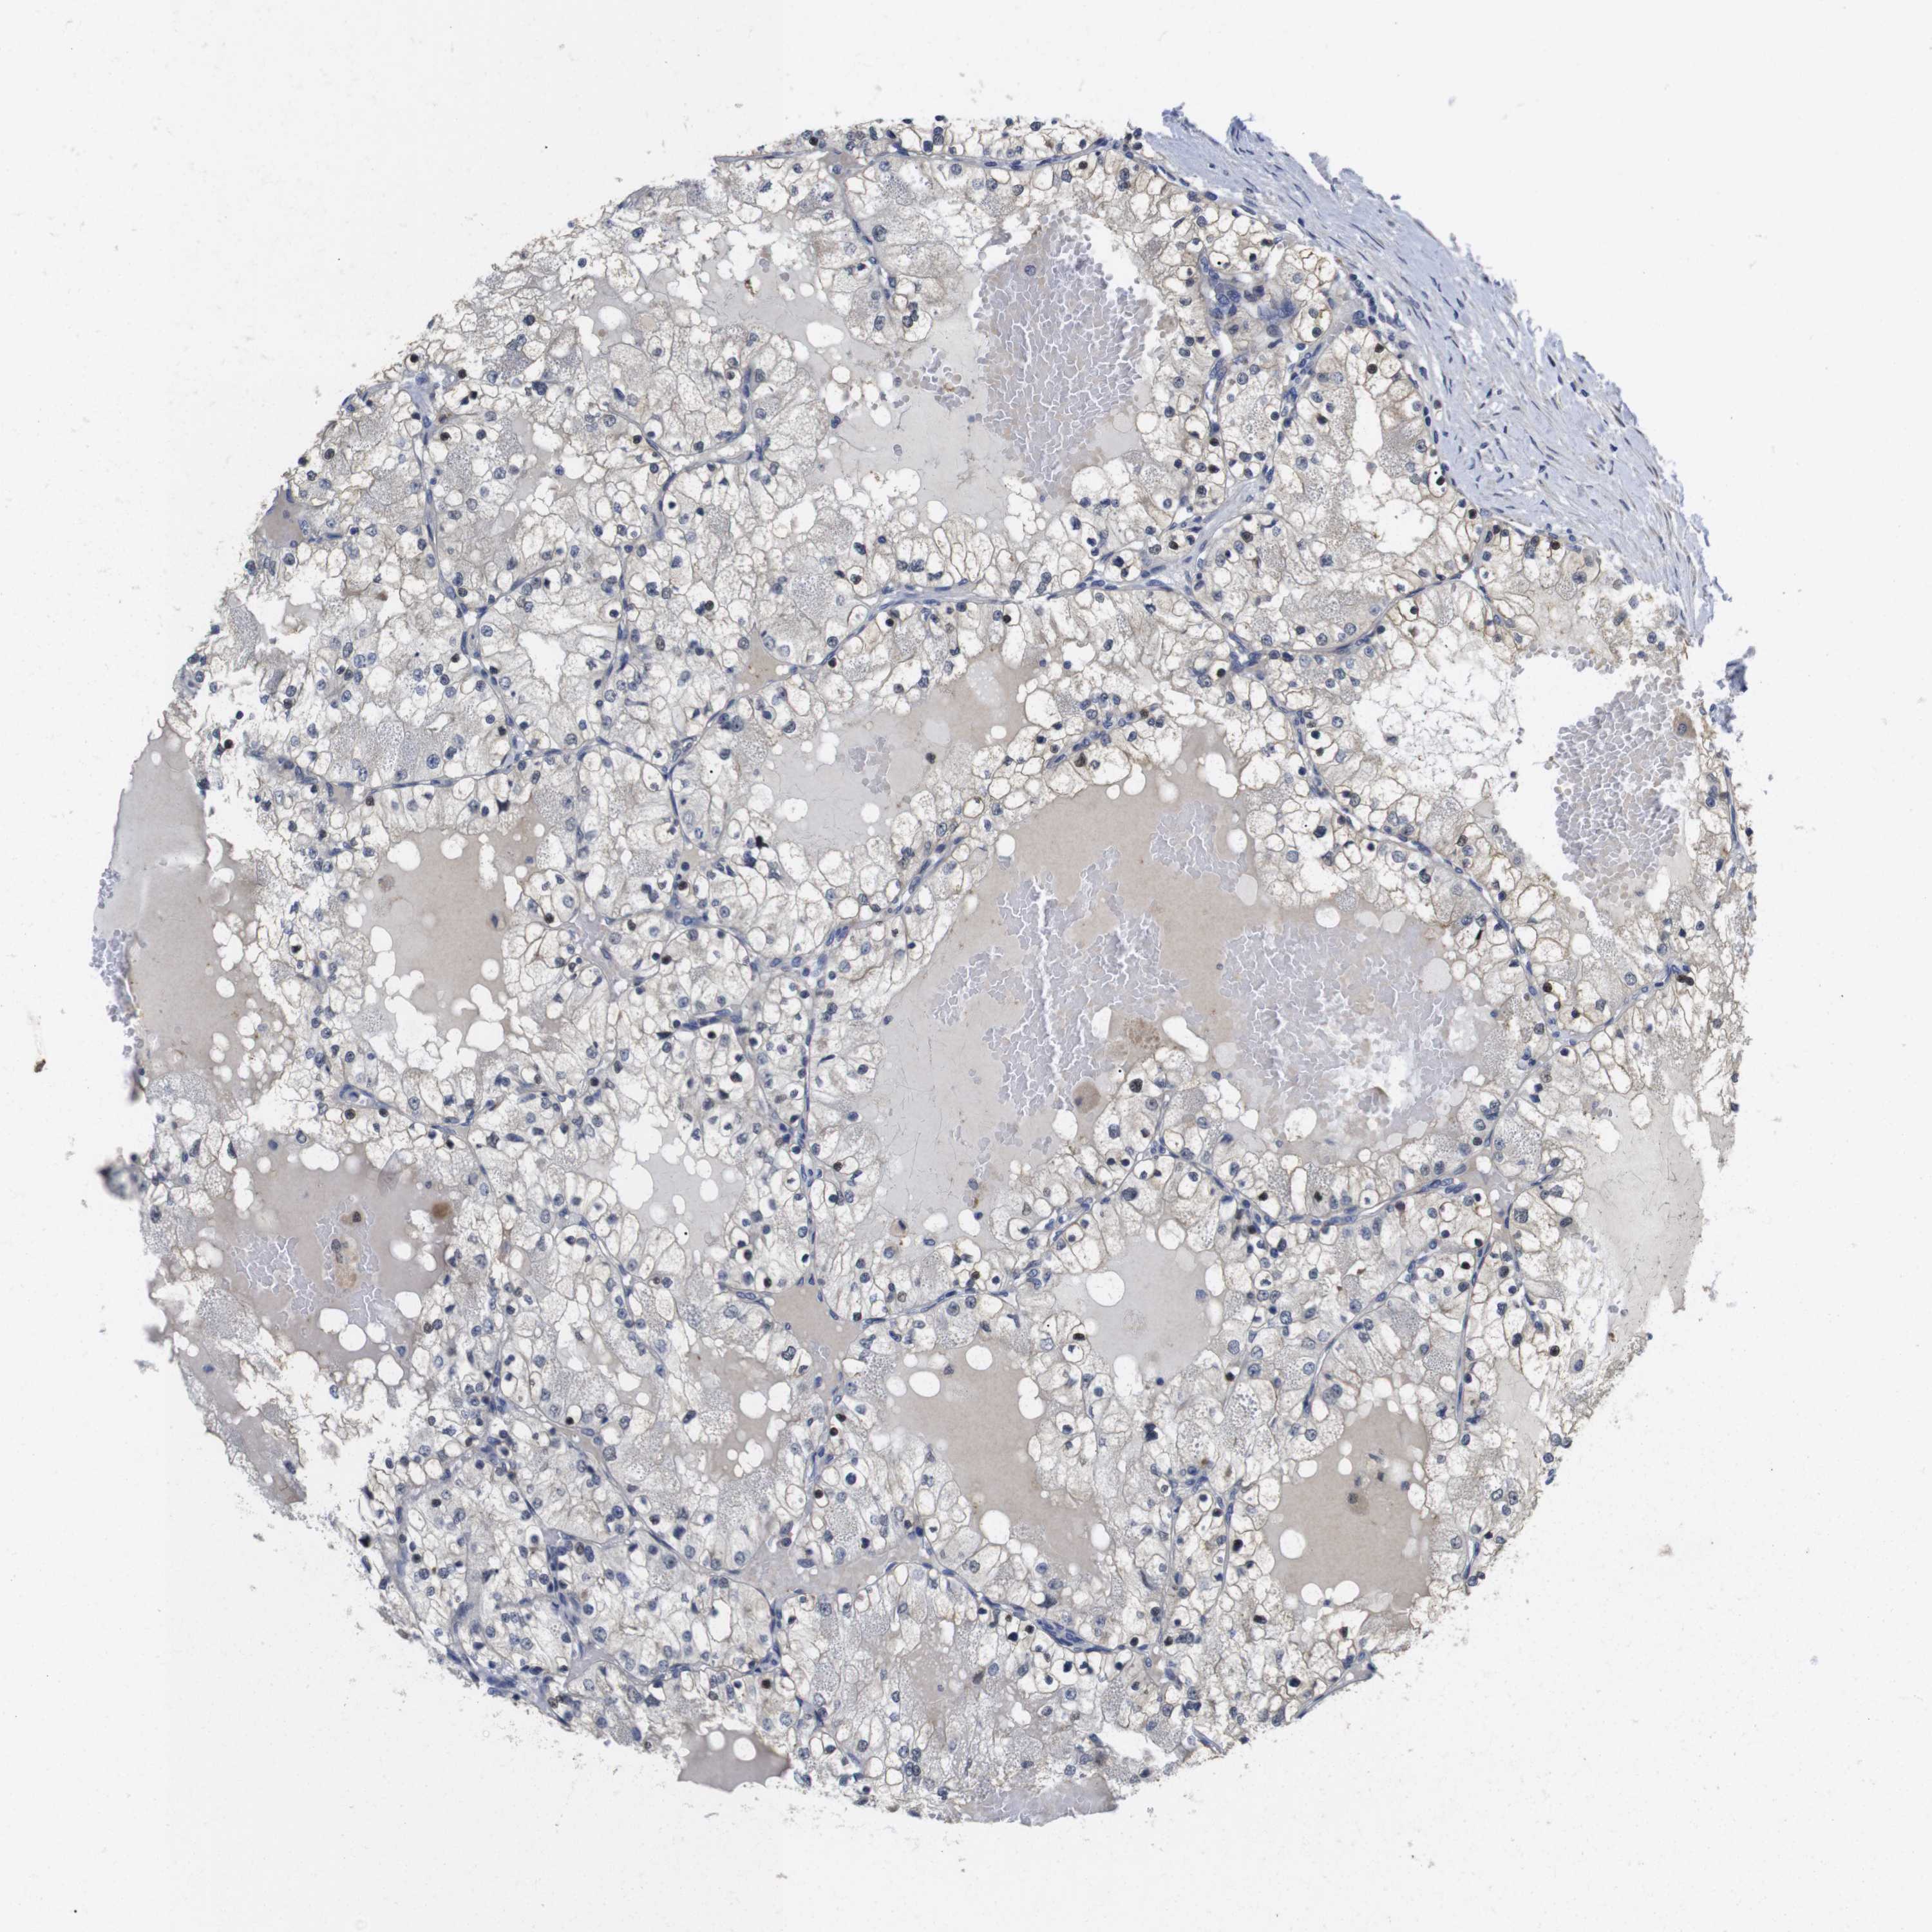

KIDNEY RENAL CLEAR CELL CARCINOMA (VALIDATION) - Interactive survival scatter ploti

The Survival Scatter plot shows the clinical status (i.e. dead or alive) for all individuals in the patient cohort, based on the same data that underlies the corresponding Kaplan-Meier plots. Patients that are alive at last time for follow-up are shown in blue and patients who have died during the study are shown in red.

The x-axis shows the expression levels (FPKM) of the investigated gene in the tumor tissue at the time of diagnosis. The y-axis shows the follow-up time after diagnosis (years). Both axes are complimented with kernel density curves demonstrating the data density over the axes. The top density plot shows the expression levels (FPKM) distribution among dead (red) and alive patients (blue). The right density plot shows the data density of the survived years of dead patients with high and low expression levels respectively, stratified using the cutoff indicated by the vertical dashed line through the Survival Scatter plot. This cutoff is automatically defined based on the FPKM cutoff that minimizes the p-score. The cutoff can be changed by dragging the vertical line or by entering a cutoff value in the square labeled "Current cut-off".

Under the Survival Scatter plot the p-score landscape (black curve; left axis) is shown together with dead median separation (red curve; right axis). Dead median separation is the difference in median mRNA expression between patients who have died with high and low expression, respectively. It is calculated as follows: median FPKM expression of dead patients with high expression - median FPKM expression of dead patients with low expression. This is intended to aid the user in visually exploring custom cutoffs and the associated p-scores and dead median separation.

Individual patient data is displayed and can be filtered by clicking on one or more of the category buttons on the top of the page. Categories describing expression level and patient information include: high, low, alive, dead, female, male and tumor stages. The scale of the x-axis can be toggled between linear and log-scale by clicking on the "x log" button. Mouse-over function shows TCGA ID, patient information and mRNA expression (FPKM) for each patient.

& Survival analysisi

Kaplan-Meier plots summarize results from analysis of correlation between mRNA expression level and patient survival. Patients were divided based on level of expression into one of the two groups "low" (under cut off) or "high" (over cut off). X-axis shows time for survival (years) and y-axis shows the probability of survival, where 1.0 corresponds to 100 percent.

FNTA is not prognostic in Kidney Renal Clear Cell Carcinoma (validation)

Best expression cut offi

Based on the FPKM value of each gene, patients were classified into two groups and association between prognosis (survival) and gene expression (FPKM) was examined. The best expression cut-off refers the FPKM value that yields maximal difference with regard to survival between the two groups at the lowest log-rank P-value. Best expression cut-off was selected based on survival analysis .

When clicking on this number, the vertical dashed line indicating cut-off, the interactive survival plot, and the Kaplan-Meier curve will be adjusted to show results based on the best expression cut-off.

: 52.28

TCGA RNA samplesi

RNA-seq data is reported as average FPKM (number Fragments Per Kilobase of exon per Million reads), generated by the The Cancer Genome Atlas (TCGA) .

Normal distribution across the dataset is visualized with box plots, shown as median and 25th and 75th percentiles. Points are displayed as outliers if they are above or below 1.5 times the interquartile range. FPKM values of the individual samples are presented next to the box plot.

Average pTPM 45.4

Number of samples 100